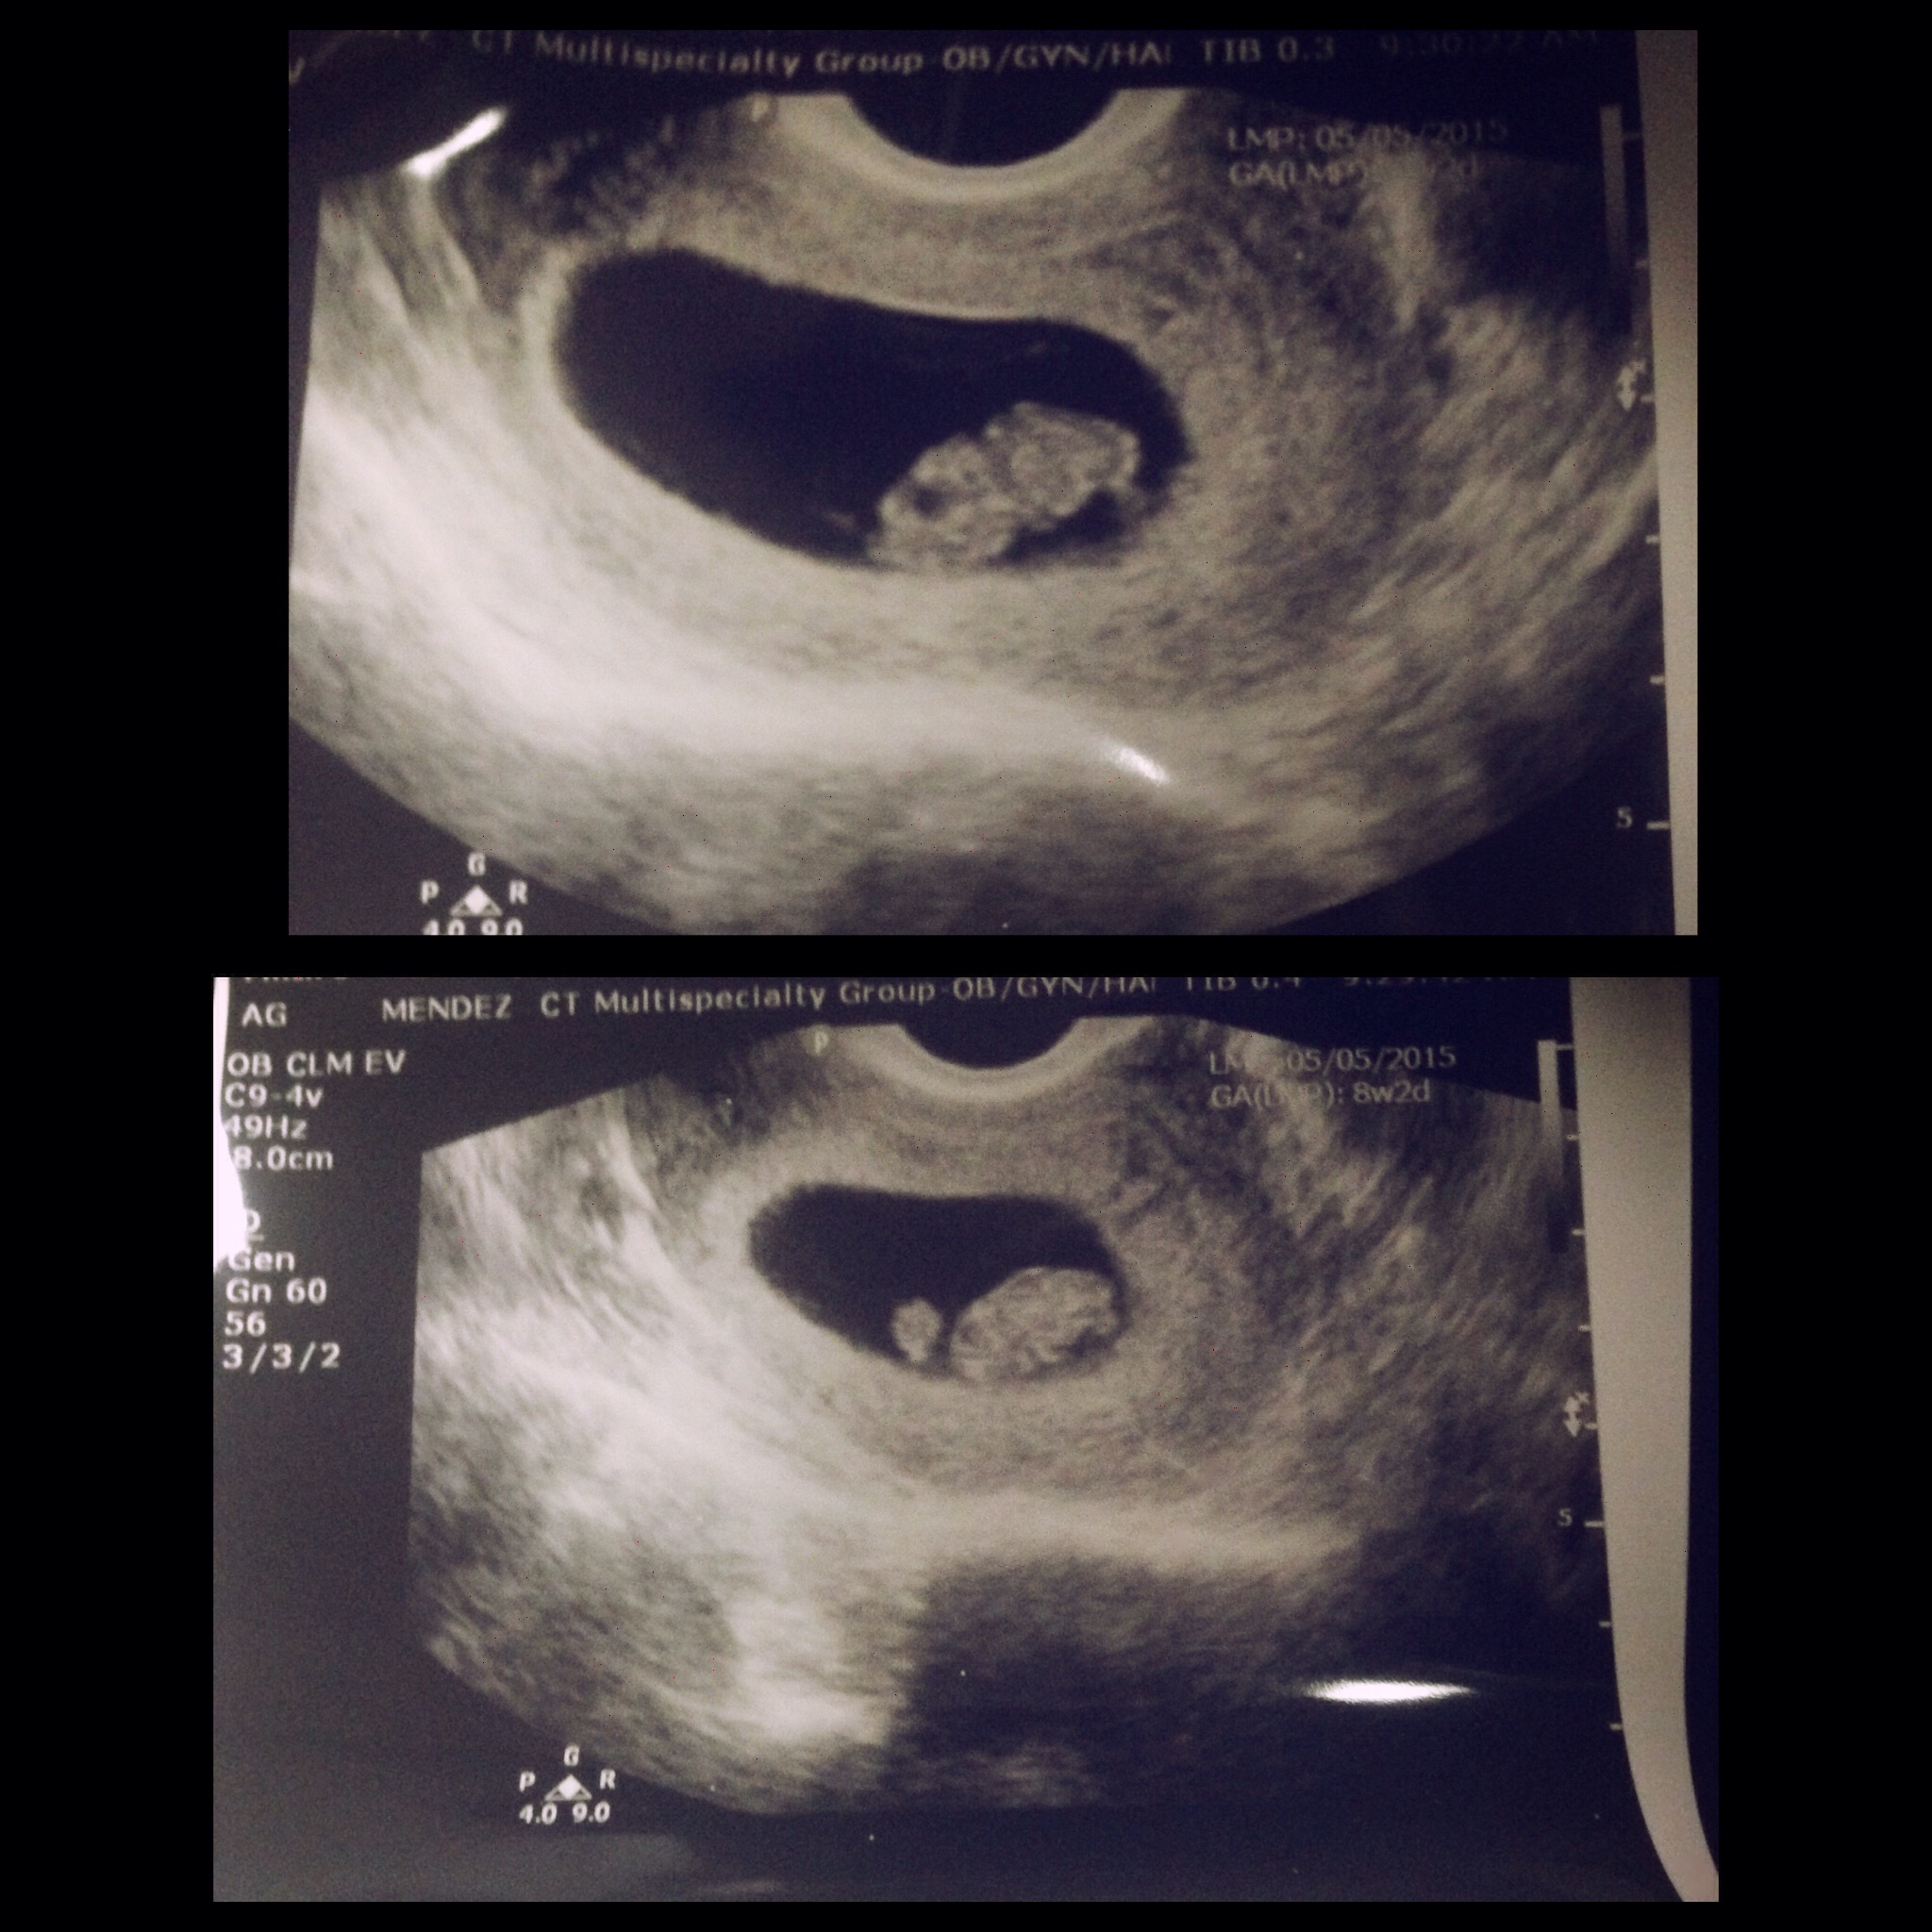

Omg these pics are so beautiful and exciting! I'm so happy for you all and know you all will be great moms here. They really do look just like gummy bears!! Can't wait until my July 16 appt!!

• Our sweet bean :) at 8 weeks 5 days